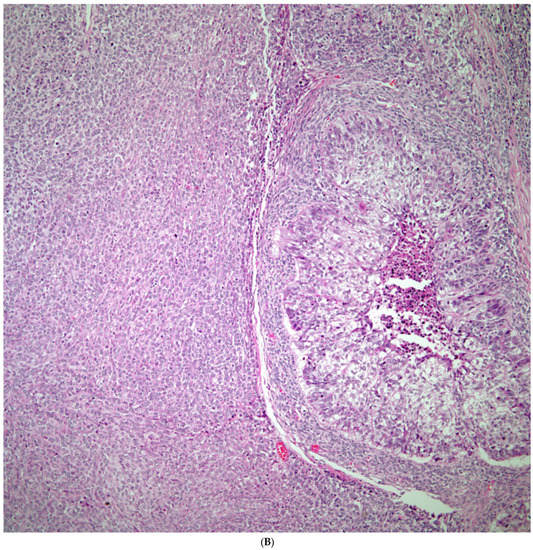

Sarcomatoid carcinomas: These tumors show a tightly packed spindle cell proliferation composed of slender cells with fusiform nuclei and inconspicuous nucleoli, replacing normal lung parenchyma. The tumors are well delimited but not encapsulated (Figure 1). Cellular atypia is variable and may show areas of mild to moderate to marked atypia. Mitotic figures also vary and may be inconspicuous or may be evident with the presence of atypical mitotic figures (Figure 2A,B). In high-grade tumors, the presence of necrosis and hemorrhage is prominent and is mixed with the neoplastic component. Important to recognize is that sarcomatoid carcinomas may be associated with areas of otherwise conventional non-small cell carcinoma such as adenocarcinoma or squamous cell carcinoma (Figure 3A,B). In addition, sarcomatoid carcinoma may also show the presence of bizarre giant cells admixed with the spindle cell component (pleomorphic carcinoma) (Figure 4).

Figure 1.

Sarcomatoid carcinoma of the lung showing a well circumscribed tumor replacing lung parenchyma.